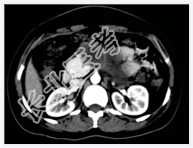

- [材料题] 患者,女性,31岁,反复上腹部疼痛1年,加重1天入院。B超示胰腺体尾部囊性病变,性质待定。行上腹部CT增强扫描。

- 简答题1、请问该患者诊断是什么?

- 简答题2、诊断依据是什么?

- 简答题3、鉴别诊断有哪些?